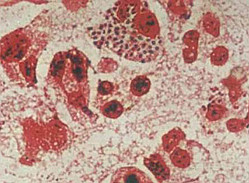

2.形态与染色 淋球菌呈卵圆形或豆形,菌体长0.6~0.8μm,宽约0.5μm。常成对排列,邻近面扁平或稍凹陷,像两粒豆子对在一起。无鞭毛,不形成芽孢。在急性感染的机体内,其形态较典型,多位于细胞浆内。慢性期则在细胞外。淋球菌革兰染色阴性。用碱性美蓝染色时,菌体呈蓝色。用Pappehheim Saathof染色时,菌体呈红色,背景为天蓝色,十分清晰。